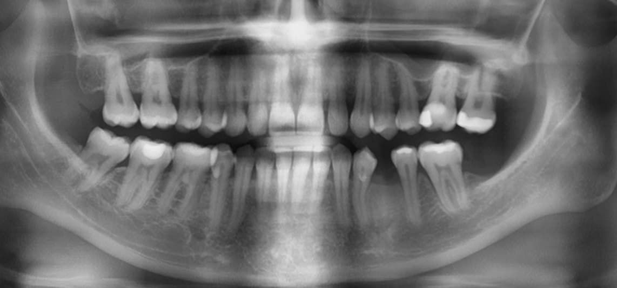

Вот так выглядит ортопантомограмма человека, у которого пародонт еще не повреждён, но уже определяется гингивит — воспалительный процесс, охватывающий всю десну или только её часть.

В лёгкой степени тяжести деструкция костной ткани — не более 1/3 от длины корней зубов. Пародонтальные карманы при этом — не более 4 мм, а патологической подвижности зубов пока ещё нет.

Вот тут уже пародонтит средней степени тяжести. Карманы — от 4 до 6 мм, деструкция костной ткани перегородок — на 1/3-1/2 длины корней. Появилась патологическая подвижность зубов І-ІІ степени.

И финальная стадия — тяжёлый генерализованный пародонтит. Тут уже пародонтальные карманы глубже 6 мм, костная ткань альвеолярных перегородок уничтожена более чем наполовину. Зубы при этом имеют патологическую подвижность ІІ-ІІІ степени. Просто для понимания: при III степени зуб уже свободно вращается вокруг своей оси, а не просто качается.